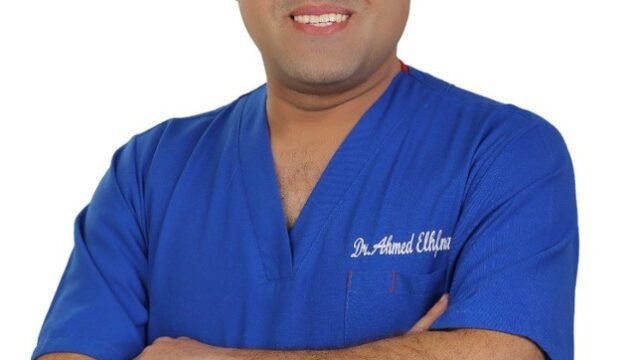

الدكتور أحمد الحفناوي – استشاري الأعصاب والخبرات العصبية الدقيقة في إيسن Holsterhausen

Neurologe

- Address : Hufelandstraße 55, 45147 Essen, Deutschland

- Phone Number : 0201 7236302